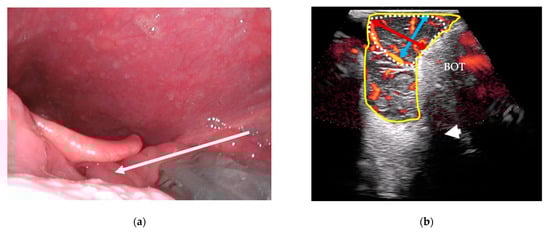

Following clinical examination, included patients will be offered combined transoral and transcervical US of the oropharynx during the initial work-up as an extension of the clinical work-up. This will be performed prior to any available T-site histopathology results. US will be performed blinded to any cross-sectional imaging. To perform the transoral US, a patient seated upright in an examination chair will receive topical anesthetic spray applied to both palatine tonsils and the posterior portion of the tongue using xylocaine (10 mg/dose). Patients are informed that eating or drinking following local anesthesia should be postponed for up to one hour due to the risk of aspiration. Patients are instructed to swallow the anesthesia. A sheathed or disinfected “hockey-stick” or small-footprint US transducer is advanced into the patient’s mouth and placed on top of the suspected palatine tonsil in the transverse plane (Figure 1a,c) with a gentle swiping motion from the cranial to caudal pole. The transducer is rotated to the sagittal plane by positioning the tip of the transducer caudally (Figure 1b,d) and a swipe is performed from the lateral to the medial edge. The procedure is repeated contralaterally. Power Doppler is performed on both palatine tonsils. If a lingual tonsil tumor is suspected, a transoral US is attempted (Figure 2).

Figure 2. Transoral US of the lingual tonsils: (a) a sheathed US transducer placed on the left lingual tonsil (arrow: swipe direction lateral-to-midline) in the sagittal plane; (b) sagittal US image with Power Doppler of the lingual tonsil (yellow outline), a tumor-suspected area (dotted outline), underlying base of tongue musculature (BOT), and the hyoid bone’s acoustic shadow (white arrowhead). The craniocaudal (blue bi-directional arrow) and anteroposterior (red bi-directional arrow) diameters are shown on the tumor-suspected area.

All US tumor measurements will be registered blinded to MRI and PET/CT. Small tumors will be measured transorally if they fit within the field-of-view of the transoral US transducers. In transverse transoral US of the palatine tonsils, the medial pterygoid muscle will serve as a lateral landmark (Figure 1c): the mediolateral diameter will be measured from the medial pterygoid muscle towards the tonsil’s medial surface. A perpendicular measurement will be performed for the anteroposterior diameter (Figure 1c). In sagittal view, the length of the tonsil tumor from the upper to lower pole will be measured as the craniocaudal diameter (Figure 1d). For the lingual tonsil, the hyoid bone will serve as a caudal landmark for the craniocaudal tumor diameter (Figure 2b). A perpendicular anteroposterior diameter will be measured through the tumor from the posterior surface of the lingual tonsil in the direction of the tongue apex. The mediolateral diameter is more difficult to measure transorally due to technical limitations of the US transducers. Instead, this diameter will be measured transcervically if the tumor can be visualized.